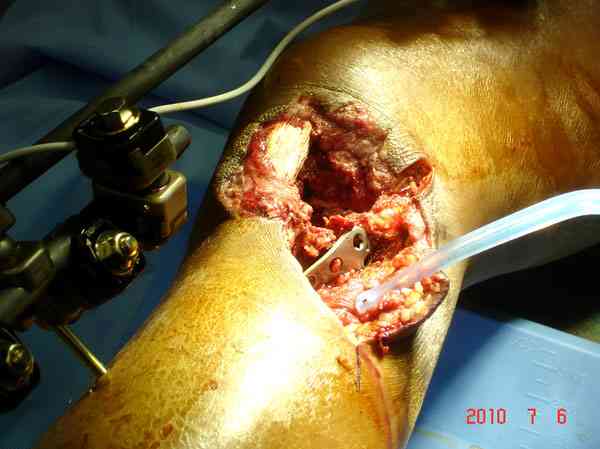

Здесь применение материала Plexur http://www.plexur.com для пластики при дефектах кости у больной с огнестрельной раной латерального тибиал плато с повреждением малоберцового нерва. Несмотря на интактный медиальный мышелок, для профилактики от вальгуса установлен АВФ и сделана ангиограмма.

После нескольких обработок и вакуумирования, поэтапно сделана фиксация тибиального бугра шурупами. И окончательную фиксацию закончили латеральной пластиной для тибиал плато и установкой пластического материала.

Для закрытия мягкотканых дефектов привлечена другая служба.